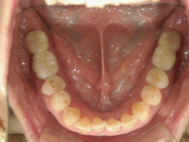

症例写真